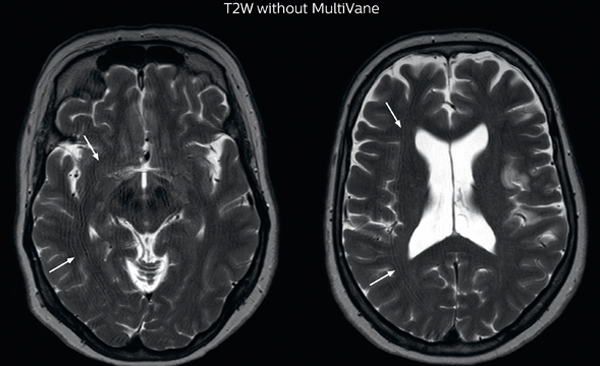

MRI motion artifact reduction in brain

The images made with MultiVane XD show significant reduction in motion artifact compared to the T2-weighted images without MultiVane below them.

Scanned on Ingenia 3.0T

Trevor Andrews, PhD, explains that the team compared motion artifacts seen in the brain with MultiVane XD and with T2-weighted TSE. “In nine out of the ten datasets in our studywe saw clear improvementswith MultiVane XD, while in the tenth dataset image qualitywas comparable. The MultiVane XD sequence is now used in the majority of patients that present at UVM for brain MRI.”

“We saw MultiVane XD provide remarkable improvement, not only for artifacts caused by patient motion, but also for the extent of pulsation artifacts in the basal cisterns. Based on these results, we have added the MultiVane XD sequence to our brain studies,” says Dr. Nickerson.

“MultiVane XD is especially useful when imaging patients with diseases that cause white matter changes on T2-weighted images, such as MS, small vessel disease, vasculitis and sarcoidosis,” says Dr. Nickerson. “Many of these are only visible on T2-weighted or FLAIR images, and sometimes aren’t even seen with FLAIR images. However, when using MultiVane XD and we don’t see any motion on the rest of the scan, but still do see a signal abnormality, we can probably attribute that to a real disease process, rather than an artifact.”